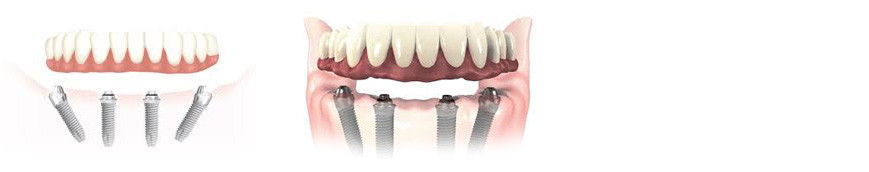

El All on Four es un técnica avanzada de implantologia con amplia evidencia científica con la que somos capaces de rehabilitar de manera completamente fija casos con perdida ósea severa, sin injertos de hueso y en menos tiempo. En una sola cirugía realizamos la extracciones de los dientes infectados si existen, colocamos los cuatro implantes y tomamos las medidas para la confección de la prótesis provisional completamente fija y en solo 24 horas es colocada en la boca del paciente. Pasados 3-4 meses se procede a tomar las impresiones definitivas y colocación de la prótesis definitiva de porcelana. Esta técnica la realizamos con la marca líder en implantologia mundial Nobel Biocare. Pida cita en nuestra clínica y le ofreceremos el plan de tratamiento adecuado para su caso.